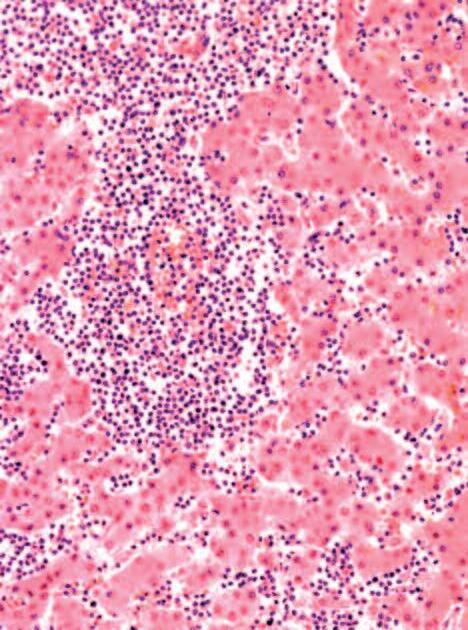

Immagine al microscopio di cellule leucemiche. Le sfere rosse del pacmen rappresentano gli enzimi collagenasi.

Questo vale anche per le cellule leucemiche. Una caratteristica di questa forma di tumore del sangue è l’eccesso di produzione di globuli bianchi, i pazienti affetti da leucemia muoiono principalmente, perché queste cellule bloccano la circolazione del sangue. In molti casi i leucemici muoiono per il cedimento di vari organi, in particolare ‘gli organi filtro’: il fegato e la milza. Milioni di globuli bianchi invadono questi organi attraverso il flusso sanguigno. Queste cellule cancerose producono immense quantità di enzimi che digeriscono il collagene, digerendo letteralmente questi organi dall'interno.

La foto nella pagina a fianco mostra una sezione trasversale al microscopio del fegato di un paziente con ‘leucemia linfatica’. Ciascuno dei piccoli puntini viola nella foto è un globulo bianco (in questo caso linfocita) che ha invaso il tessuto del fegato (aree rosa).

Considerando l’enorme quantità di questi puntini viola e il numero di enzimi che assimilano il collagene che ciascuno produce, è facile prevedere l’ingente distruzione del tessuto connettivo e il danno apportato all’organo da questo tipo di cancro.

La leucemia è un buon esempio di come la comprensione dei meccanismi delle cellule tumorali, la produzione di enzimi che digeriscono il collagene da parte dei globuli bianchi, per poter studiare terapie efficaci.

Immagine al microscopio della leucemia linfatica

Globuli bianchi affetti di cancro (linfociti) invadono il fegato L’enorme quantità di collagenasi prodotte da queste cellule distruggono l’organo e causano insufficienza epatica.